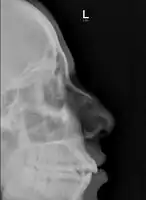

| Plain X-ray showing a nasal fracture | |

The most common causes include assault, trauma during sports, falls, and motor vehicle collisions.[1] Diagnosis is typically based on the signs and symptoms; with plain X-ray rarely of benefit.[1][6] CT scan may be useful if concerns of other fractures or complications are present.[6][4]

Nasal fractures are usually identified visually and through physical examination.[1] Medical imaging is generally not recommended.[1][2] A priority is to distinguish simple fractures limited to the nasal bones (Type 1) from fractures that also involve other facial bones and/or the nasal septum (Types 2 and 3). In simple Type 1 fractures X-Rays supply surprisingly little information beyond clinical examination. However, diagnosis may be confirmed with X-rays or CT scans, and these are required if other facial injuries are suspected.[2]